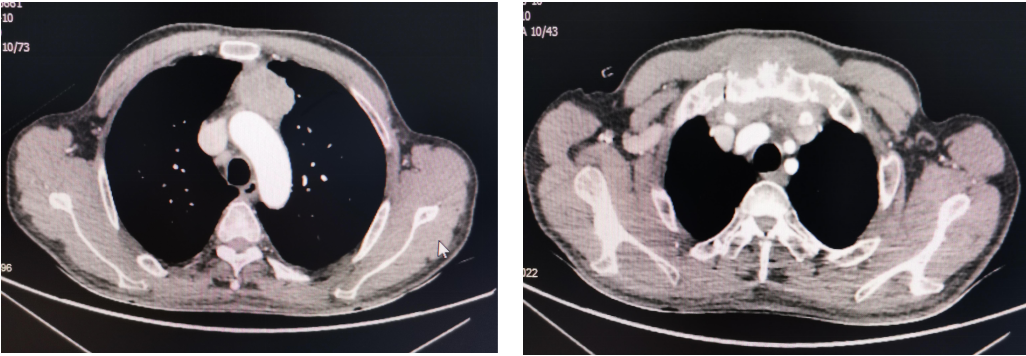

患者,男性61岁,于入院前半年出现前胸壁疼痛不适,活动时加重,当地医院行胸部正位片未见明显异常,积极止疼治疗,效果不佳,遂来我院就诊。胸外科主任医师蒋鹏查体发现胸骨柄凸起,压痛(+),遂行胸部CT+三维成像检查,结果提示:纵隔肿物、胸骨柄骨质破坏、双侧胸锁关受侵。头颅MRI、全身骨显像、腹部CT未见肿瘤转移。